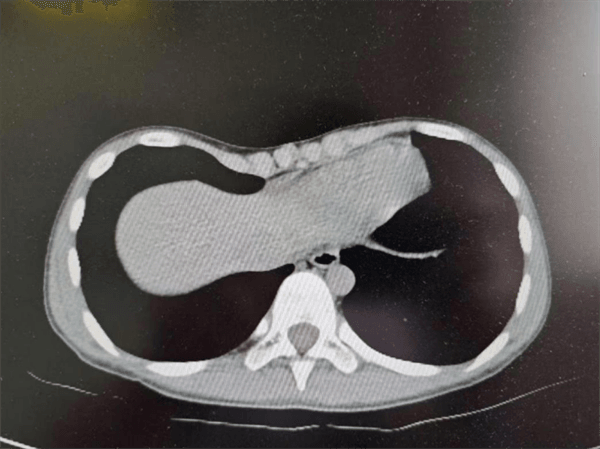

小豪父亲逐渐意识到问题的严重性,于是放暑假后带着小豪四处求医,最终来到了宝鸡市妇幼保健院儿童医院小儿外科门诊。科主任徐珂看过孩子后介绍:“你这是很典型的漏斗胸啊,怎么才来看病呀。”通过胸部CT检查显示为重度漏斗胸,需尽早通过手术进行矫正。医生向小豪父亲详细阐释:这是一种常见的先天性胸壁发育畸形,由胸骨、肋软骨及部分肋骨向脊柱方向呈漏斗状凹陷所致,通常在胸骨剑突上方凹陷最为明显。

小儿外科医生们对小豪的胸廓进行了精准测量和充分评估,经多学科联合会诊(MDT)后决定落实了手术当中的诸多细节,最终决定了手术时间。当日,小豪手术进展顺利。在胸腔镜的观察下,弧形钛合金金属支架被置入胸腔,两侧胸壁各有一个仅2cm长的手术切口,并进行了美容缝合。麻醉苏醒后,小豪安静地躺在病房,发现困扰自己的胸部疾患已成功矫正。